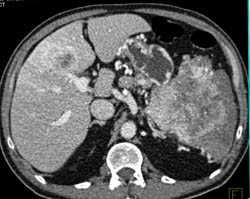

Islet Cell Tumor With Liver Metastases